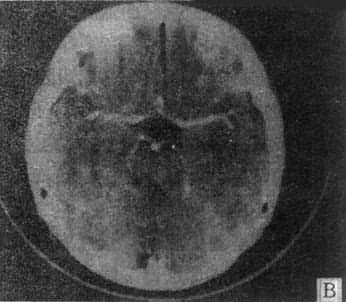

10mm底颅层面 此层面通过眦耳线上方10mm,由前向后可见眼眶上部、蝶窦和中颅凹底、枕骨及枕大孔等颅底结核。20mm蝶鞍层面 可见垂体、四脑室桥池和桥小脑角池、岩锥与内耳道、前、中和后颅凹脑组织结构。本层面重点观察垂体和后颅凹结构。(图5-1-4A)。30mm鞍上池层面 可见鞍上池呈六角星或五角星形低密度脑脊液间隙,增强CT扫描尚可见脑底动脉环在池内的分布情形(图5-1-4B)。鞍上池后方、环池四叠体池包绕部分即为中脑。40mm三脑室前部层面 重点观察内囊、基底节和丘脑区(图5-1-4C)。50mm三脑室后部层面除显示内囊、基底节和丘脑区外,同时是观察三脑室后部松果体区重点扫描层面(图5-1-4D)。60mm侧脑室体层面可观察侧脑室体部、三角区和后角(图5-1-4E);增强CT尚可见直窦上矢状窦大脑镰强化显影。70mm侧脑室顶层面 可见侧脑室顶部、大脑纵裂、脑皮质脑髓质(图5-1-4F)。80~100mm脑室上层面 脑皮、髓质、脑沟和大脑纵裂清楚显示。

图5-1-4 正常头部CT扫描

A、蝶鞍一鞍上池层面,鞍上池和后颅凹同时显示,

B、鞍上池层面增强扫描,可见颅底动脉环显形

C、第三脑室前部层面 D、第三脑室后部层面

E、侧脑室体部层面 F、侧脑室顶层面